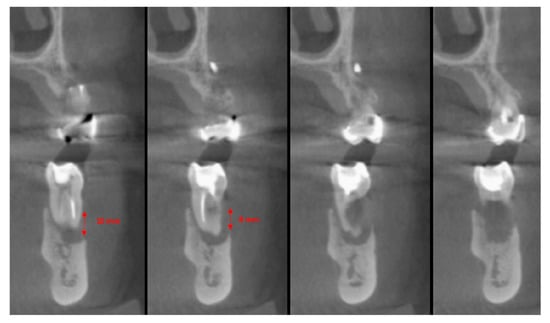

The vertical average defect was 9.16 mm, buccal lateral/palatal 7.0 mm, and mesio-distal 10.3 mm. The measurements were intraoperatively performed with a millimeter periodontal probe. The endodontic material mechanically cleaned before the tooth was placed inside the Tooth Transformer device. The endodontic material was removed using a drill bur with the attention to cut the canal in excess with the aim to remove all the cement. No surgical complications were registered. Pre and post-operative X-rays (section from CBCT) were collected from the same case (Figure 1, Figure 2, Figure 3 and Figure 4). After four months, 13 histological and histomorphometrical evaluations were performed (Figure 5). The Bone Volume/Total Volume average (BV%) was 41.47 (S.D. ± 11.51), the Residual Graft/Total Volume average (Graft%) was 16.60 (S.D. ± 7.09), and the Vital Bone/Total Bone average (VB%) was 21.89 (S.D. ± 9.72). No extraneous material (gutta-percha or cement) was detected in all samples (Table 3).

Figure 3. The cbct section in zone 36, two months after the Guided Bone Regeneration (GBR). The defect was completely filled using the endodontical treated elements site 3.5 and 3.6 (Italian teeth numeration).

Figure 4. The cbct section in zone 36 after the implants healing, six months after the GBR.